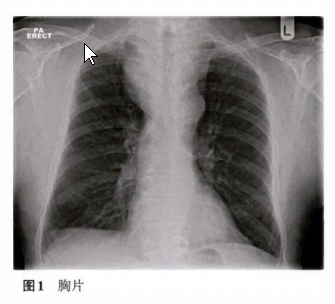

患者男性74岁,出现心悸,心电图示心房颤动。主诉胸部纹路增多,伴有醒来后偶发呼吸困难。以往有慢性阻塞性肺病及高血压伴左心室肥大。体检发现胸壁上可见明显血管外,无其他发现。胸片上见上纵隔增宽。